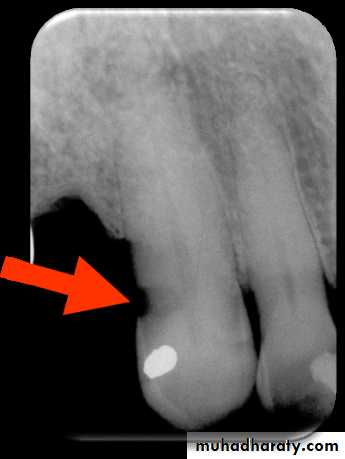

Root Surface Caries

Clinically root surface caries is easily detected on exposed root surface.The most common locations include the exposed root of the mandibular premolar and molar areas.

Radiographically the root surface caries appears as a cupped–out or crater shaped radiolucency just below the cemento-enamel junction.